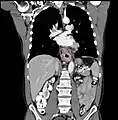

Additional testing is needed to assess how much the cancer has spread (see #Staging, below). Computed tomography (CT) of the chest, abdomen and pelvis can evaluate whether the cancer has spread to adjacent tissues or distant organs (especially liver and lymph nodes). The sensitivity of a CT scan is limited by its ability to detect masses (e.g. enlarged lymph nodes or involved organs) generally larger than 1 cm.[41][42] Positron emission tomography is also used to estimate the extent of the disease and is regarded as more precise than CT alone.[43] Esophageal endoscopic ultrasound can provide staging information regarding the level of tumor invasion, and possible spread to regional lymph nodes.

Contrast CT scan showing an esophageal tumor (axial view)

Contrast CT scan showing an esophageal tumor (coronal view)